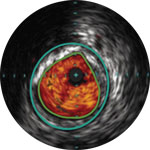

Behandlungsplan Beispiel 2

Lumen mit frischem Thrombus

Mikrokalzifizierung

Kalzifizierte Plaque mit Schallschatten

Gefäßgröße: 6 mm Durchmesser Plaquemorphologie: gemischte, thrombotische Plaque mit mittlerem Calcium Plaquegeometrie: exzentrische Läsion Position des Führungsdrahtes: wahres Lumen

Quick-Cross-Katheter: souverän komplexe Morphologien durchqueren Turbo-Power-Laser-Atherektomie: vorwärts gerichtetes, direktionales Abtragen zur Beseitigung von Thromben; Rotation für verbessertes Abtragen in kalzifizierten Läsionen AngioSculpt Scoring-Ballonkatheter: sicheres Aufweiten von Reststenosen4 Stellarex DCB: entwickelt für hohe Leistungsfähigkeit bei Kalfizifierungen